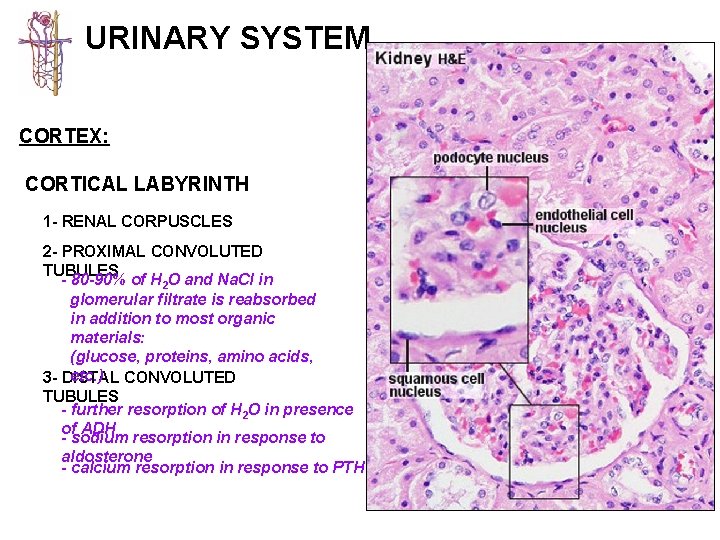

URINARY SYSTEM CORTEX: CORTICAL LABYRINTH 1 - RENAL CORPUSCLES 2 - PROXIMAL CONVOLUTED TUBULES - longer than DCT and thus more numerous - stain slightly darker and have a larger diameter than DCT - cells are larger and have an irregular luminal surface due to the presence of a “brush border” and glycocalyx 3 - DISTAL CONVOLUTED TUBULES - shorter than PCT and thus less prevalent - stain slightly lighter and have a smaller diameter than PCT - cells are smaller and cuboidal, thus more nuclei are apparent in a cross section of a DCT - luminal surface is more uniform since it lacks a brush border

URINARY SYSTEM CORTEX: CORTICAL LABYRINTH 1 - RENAL CORPUSCLES 2 - PROXIMAL CONVOLUTED TUBULES - 80 -90% of H 2 O and Na. Cl in glomerular filtrate is reabsorbed in addition to most organic materials: (glucose, proteins, amino acids, etc. ) CONVOLUTED 3 - DISTAL TUBULES - further resorption of H 2 O in presence of ADH - sodium resorption in response to aldosterone - calcium resorption in response to PTH